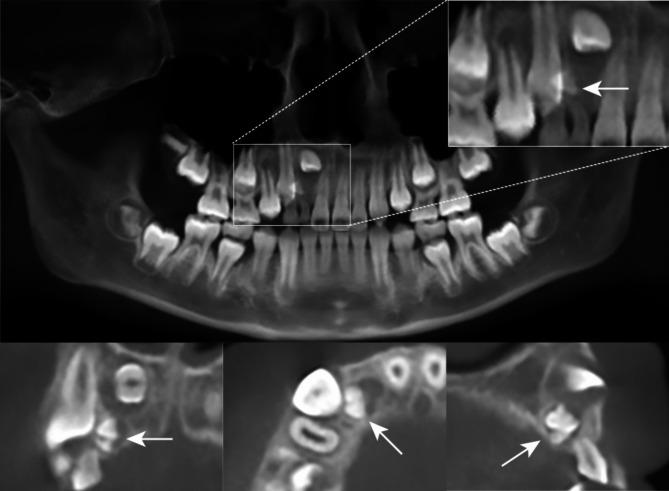

CASE PRESENTATION

An 11-year-old girl was diagnosed with Class II division 1 malocclusion and impaction of the maxillary right lateral incisor caused by an odontoma. A non-extraction treatment plan was implemented, involving first the distalization of the maxillary molars and utilization of the leeway space to create an eruption space, followed by surgical exposure and orthodontic traction, and finally, anterior teeth retraction and mandibular advancement guided by Class II elastics. After 39 months, the impacted maxillary right lateral incisor was successfully aligned, achieving Class I molar and canine relationship with a normal overbite and overjet and an improved facial profile.

病例报告

一名11岁女孩被诊断为安氏II类1分类错牙合,上颌右侧侧切牙因牙瘤而埋伏阻生。实施了不拔牙治疗方案,首先进行上颌磨牙远移并利用替牙间隙创造萌出间隙,随后进行外科开窗和正畸牵引,最后,使用II类牵引引导前牙内收和下颌前伸。39个月后,上颌右侧埋伏阻生侧切牙成功排齐,达到磨牙和尖牙I类关系,覆盖和覆牙合正常,面部轮廓得到改善。